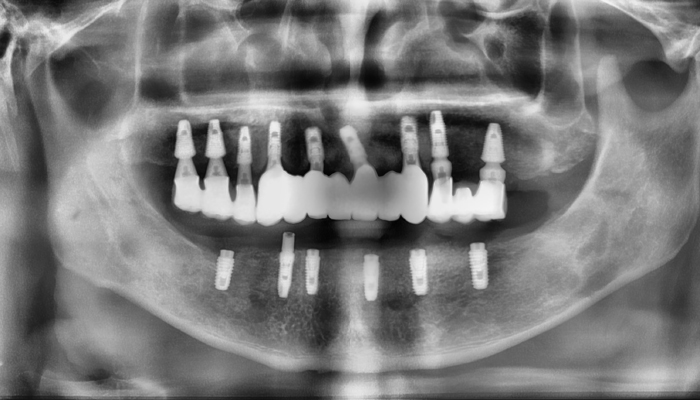

뼈이식 임플란트 전후 사례

• 식립전

식립후